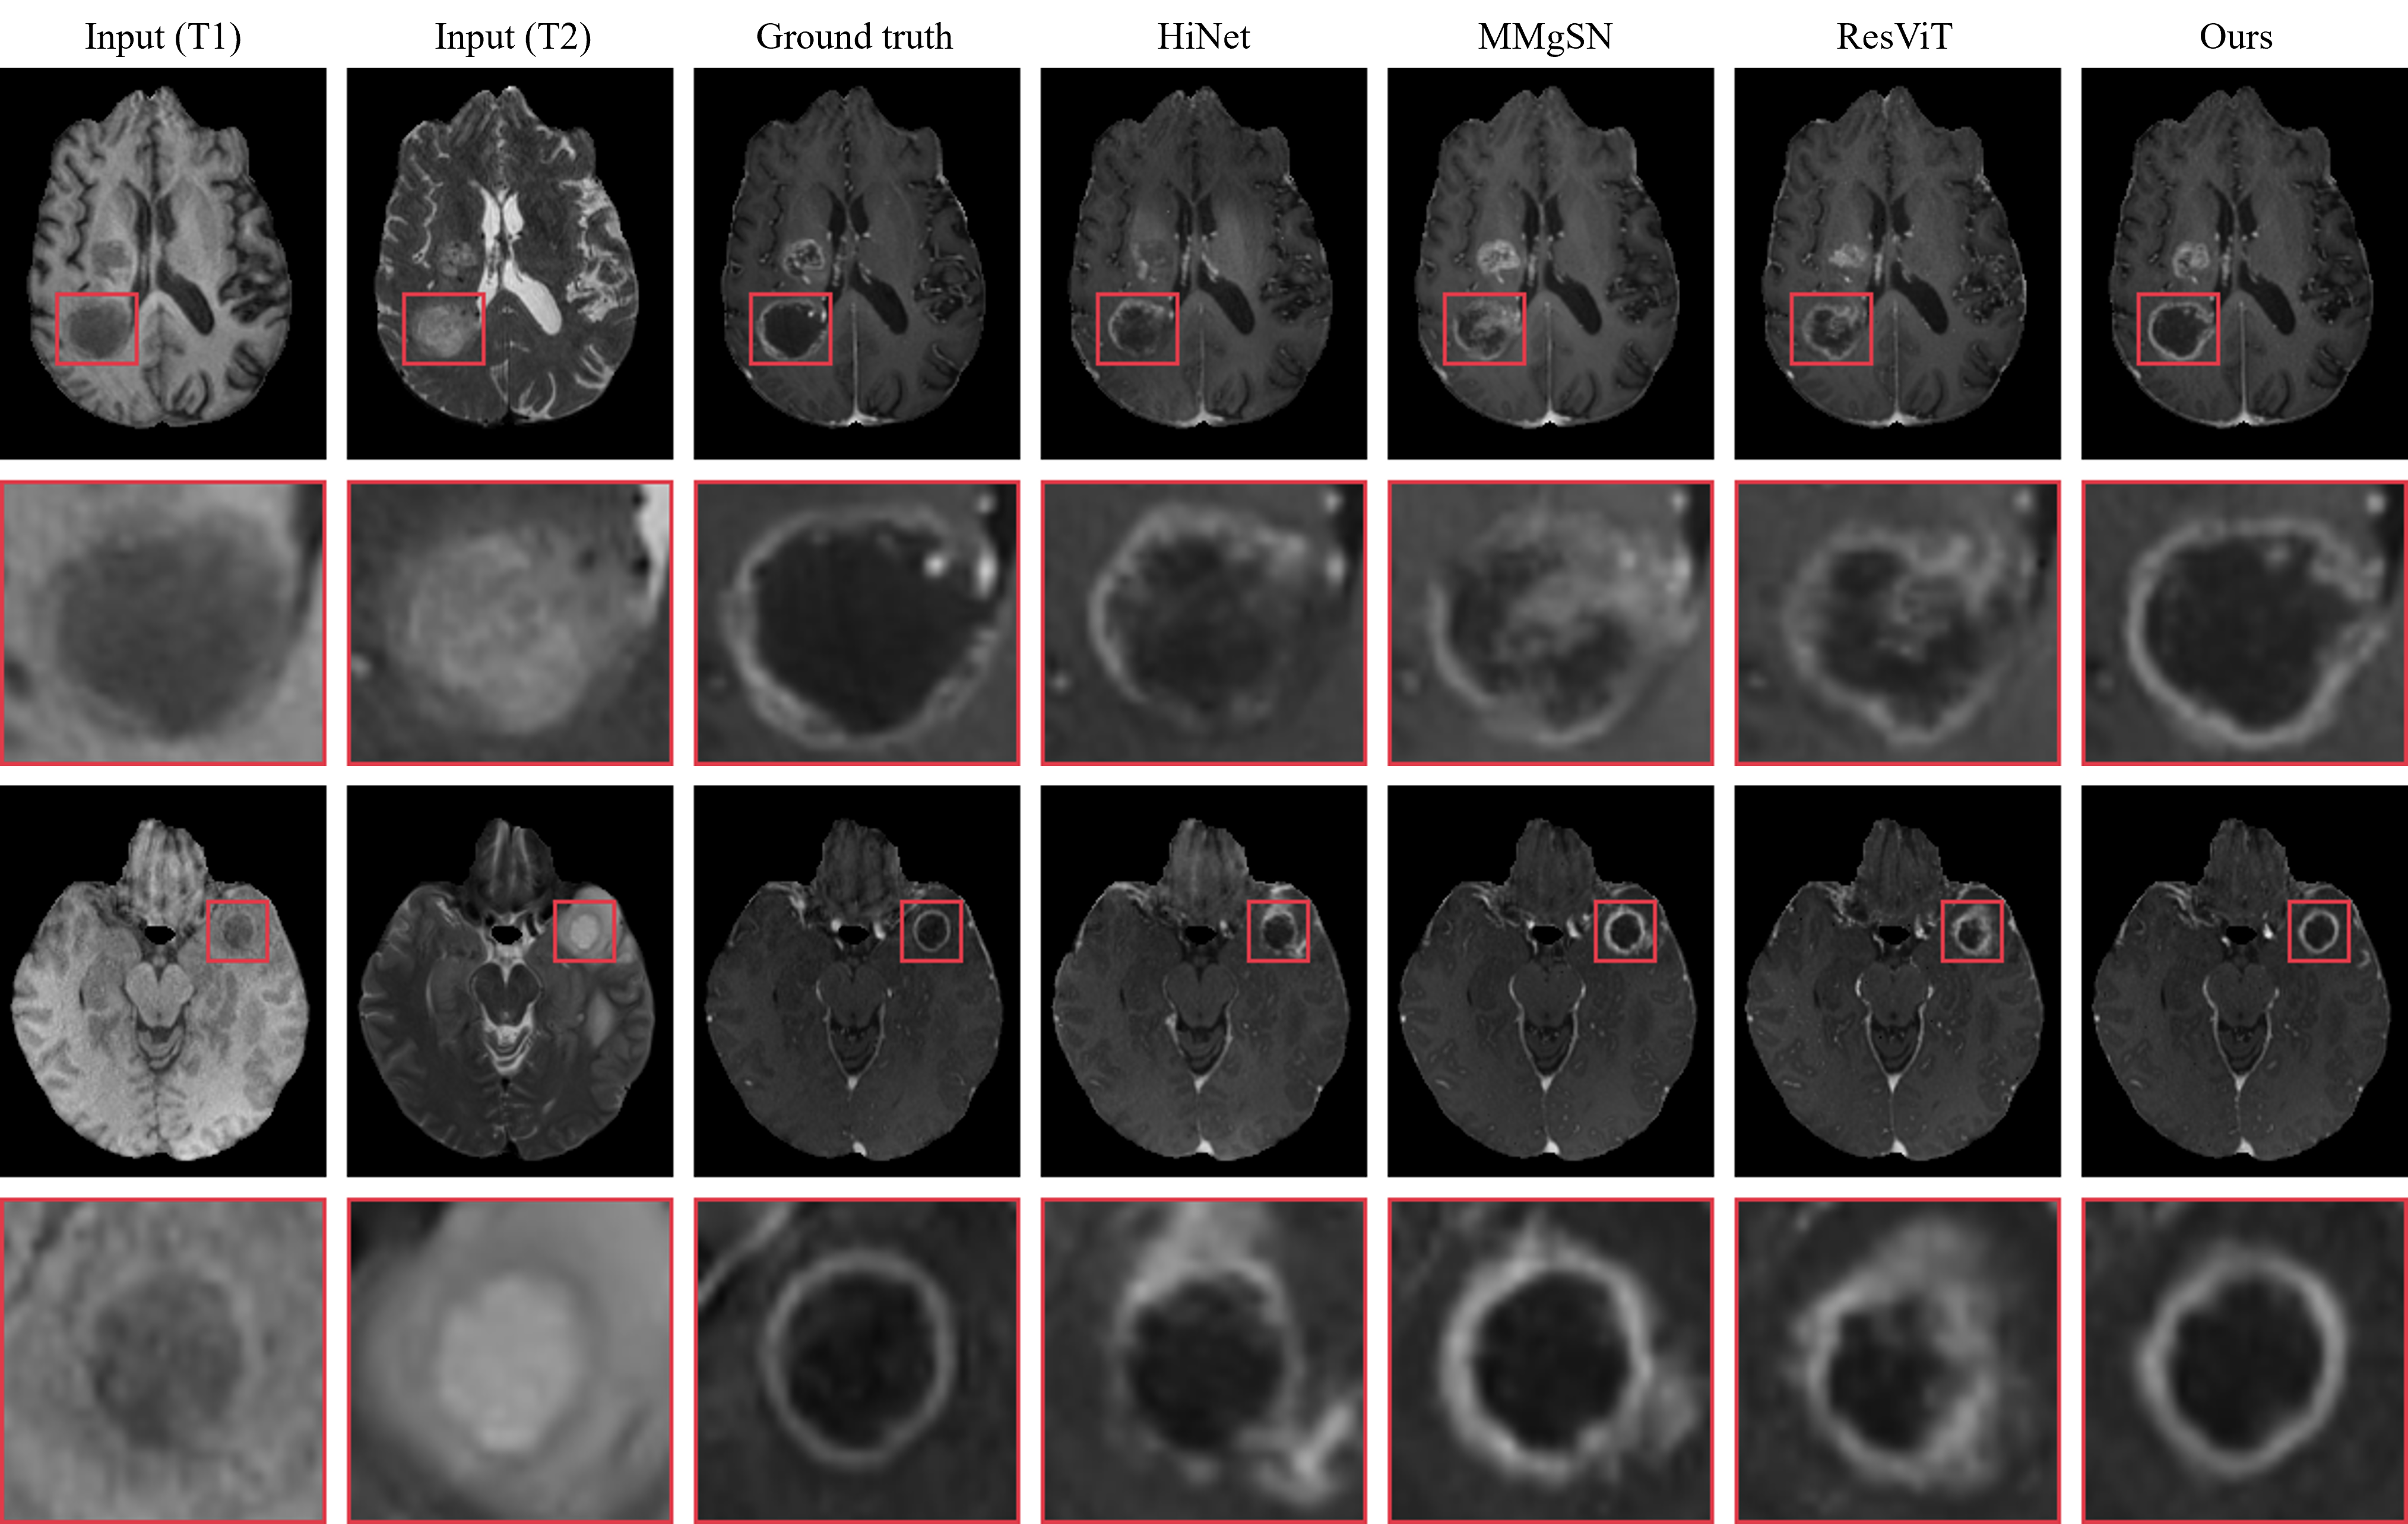

Figure 4: Visual comparison of synthesis results from all many-to-one models on the BraTS 2021 dataset. Each model takes T1 and T2 as inputs simultaneously to synthesize T1ce.

Fig. 4 compares our method with HiNet, MMgSN-Net, and ResViT in the multi-input scenario. While all methods benefit from additional input information, our model consistently produces the highest visual quality. Regardless of tumor size, our model can synthesize accurate tumor contours, while other methods generate discontinuous contours and incorrect enhancement regions. Notably, the Transformer-based ResViT model struggles with complex tumor structures due to excessive feature compression.